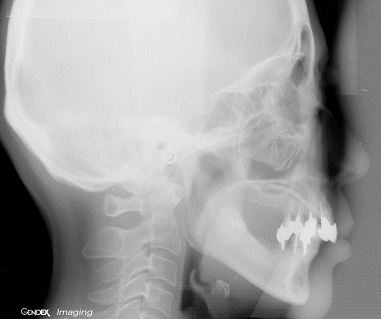

精密検査(診査診断・治療計画)

なぜこのような状態になってしまったのか?どうしたら治るのか?長期に安定させるにはどうしたら良いのか? 徹底的に検査し治療計画を立案します。 |

問診・視診、レントゲン写真の読影・分析、口腔内模型の診査、噛み合わせの検査、歯周病の検査等を行ないます。 |

CT撮影とインプラント植立部位の診査

初期治療が終わるとCTを撮影します。CTによる診断と3Dシミュレーションソフト(SIM/Plant)を活用し、インプラント植立部位の状況を把握します。インプラントが審美的、機能的、長期的に維持されるために植立位置は極めて重要です。